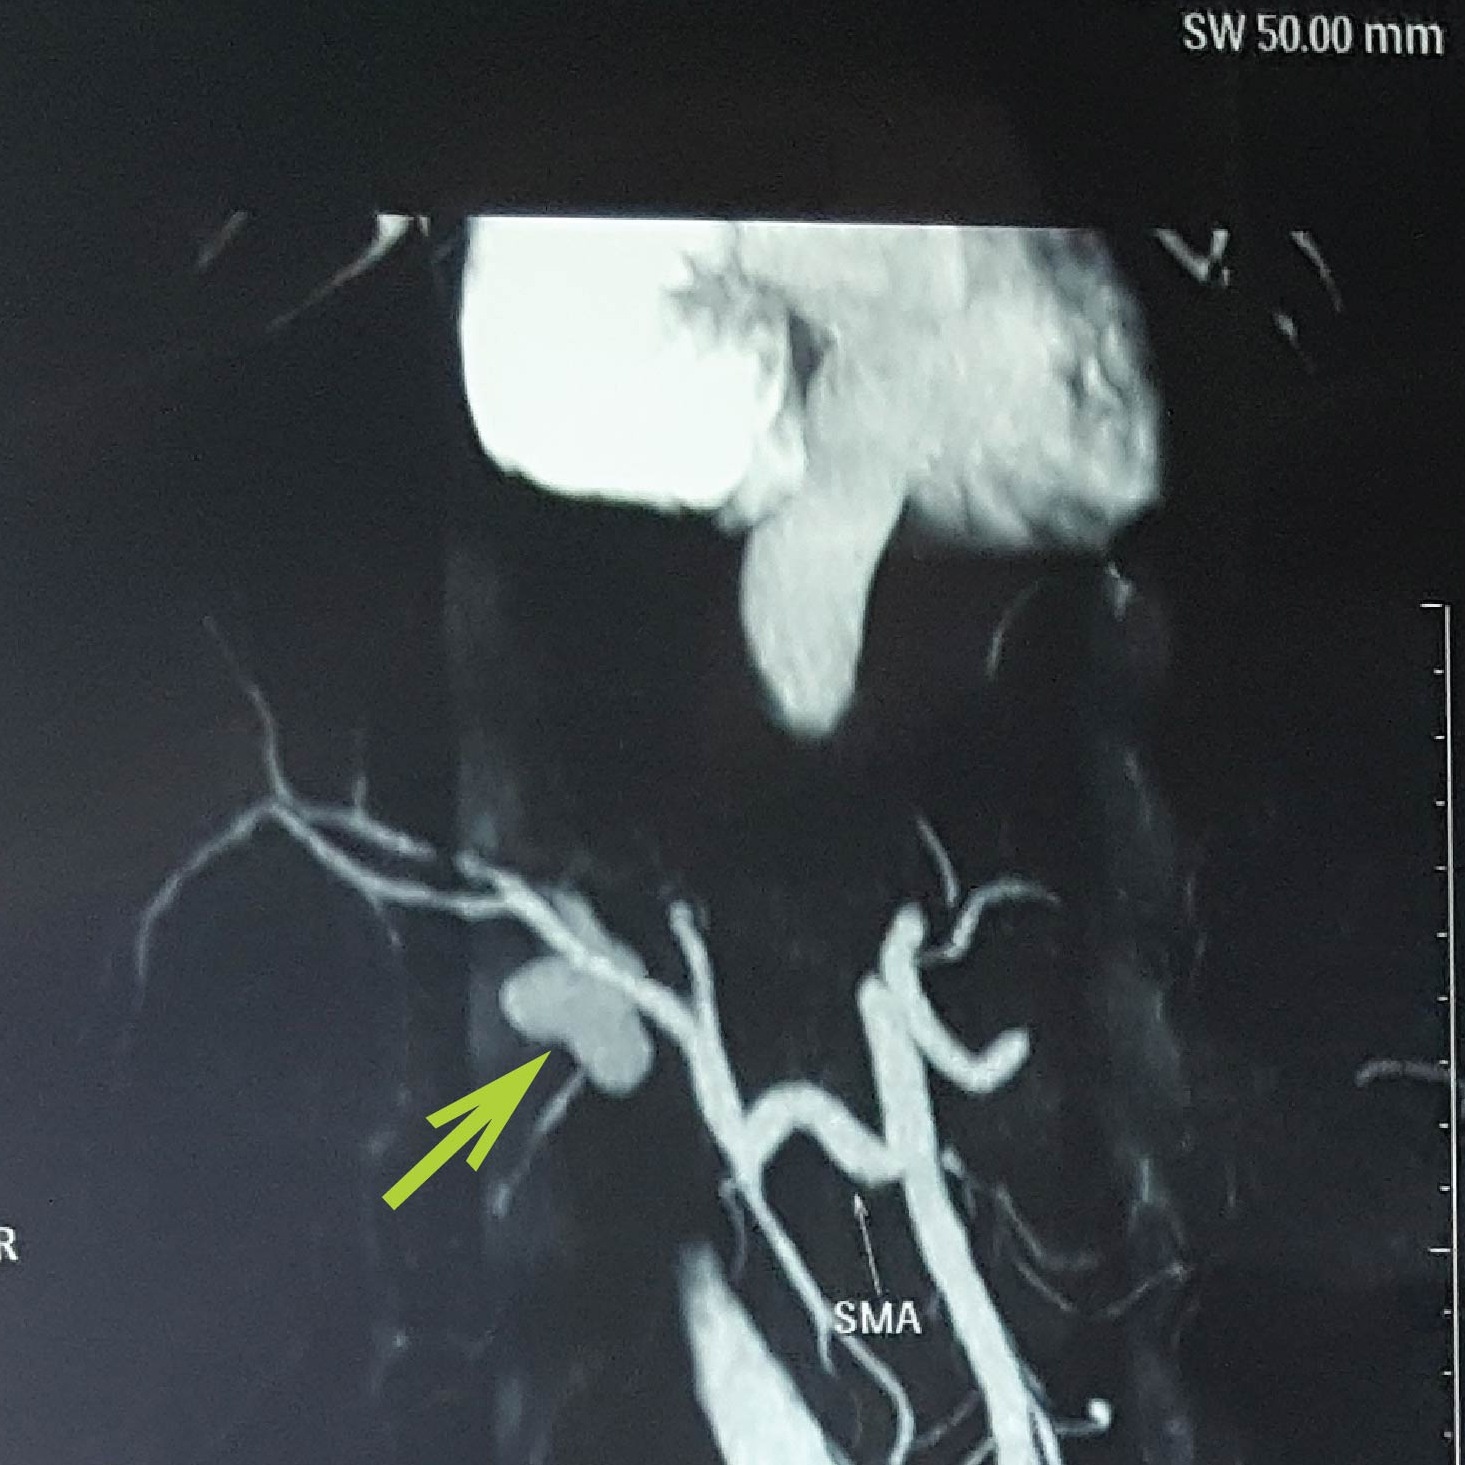

Sau khi vào cấp cứu tại BV Bình Dân, qua phim CT-scan bụng, các bác sĩ phát hiện động mạch gan của bệnh nhân bị phình, tạo thành hình túi kích thước 34 mm. Ngoài ra, bệnh nhân còn bị dị dạng cấu trúc mạch máu nuôi gan.

| Hình ảnh túi giả do phình động mạch gan của bệnh nhân. Ảnh: T.N. |

Sau hội chẩn, ca phẫu thuật can thiệp nội mạch được tiến hành. Đội ngũ y tế loại bỏ túi và mạch máu bị phình bằng phương pháp tắc mạch với keo sinh học. Phần túi phình có kích thước lớn, vách mỏng, chỉ một sơ xuất nhỏ cũng có thể làm vỡ, gây tình trạng đột tử đe dọa tính mạng người bệnh.